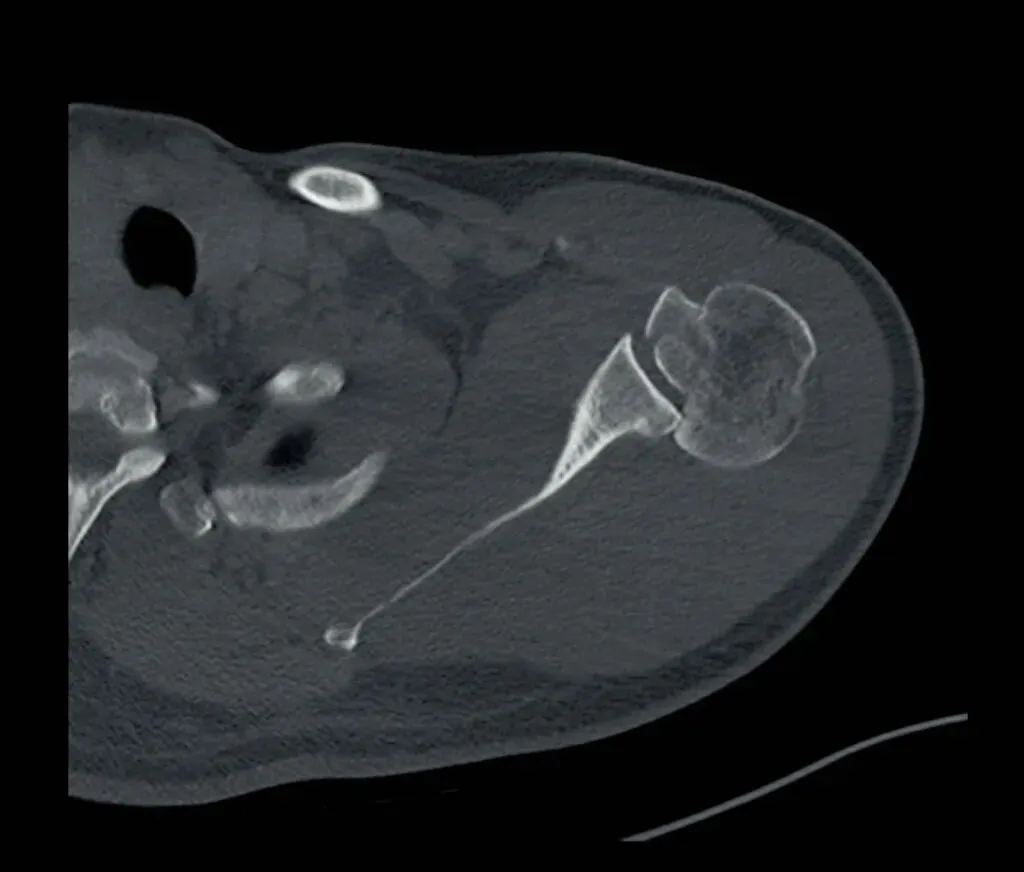

其次,我们要注意外伤患者不仅有肩关节脱位,有时还会伴随骨折出现。有一个很典型的影像学表现就是槽线征,当肱骨头撞击关节盂后缘,骨质形成压缩性骨折,表现为肱骨头内侧骨皮质与反Hill-Sachs骨折块形成的近乎平行线,称槽线征。

槽线征的识别对判断肱骨头内侧压缩性骨折至关重要。我们可以在肩关节的X线或者CT检查中清晰看到后脱位的肱骨头向关节窝的后方移位,同时也可显示肱骨头内侧受撞击形成的压缩性骨折(反Hill-Sachs骨折)。